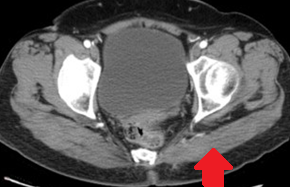

Αξονική τομογραφία κοιλίας. Φεβρουάριος 2017. Εμφανίζεται η υποτροπή του οπισθοπεριτοναϊκού αγγειοσαρκώματος (κόκκινα βέλη)